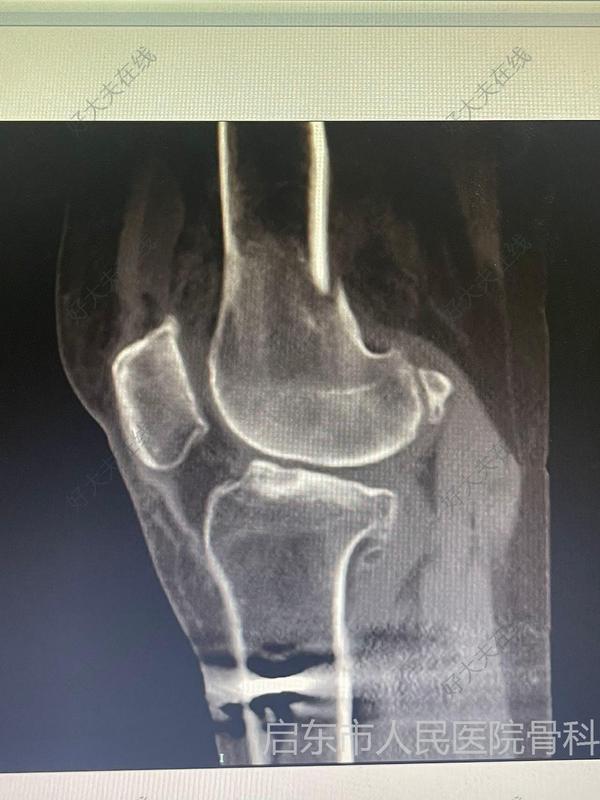

治療前88歲高齡患者,摔傷致左髖部疼痛伴活動受限2小時入院,急診拍片顯示:左側股骨轉子間骨折治療中完善術前檢查,多學科會診,入院第三天行椎管麻醉下左側股骨近端髓內釘內固定術(PFNA)治療后治療后7天術后疼痛緩解,患者可扶助行器行走